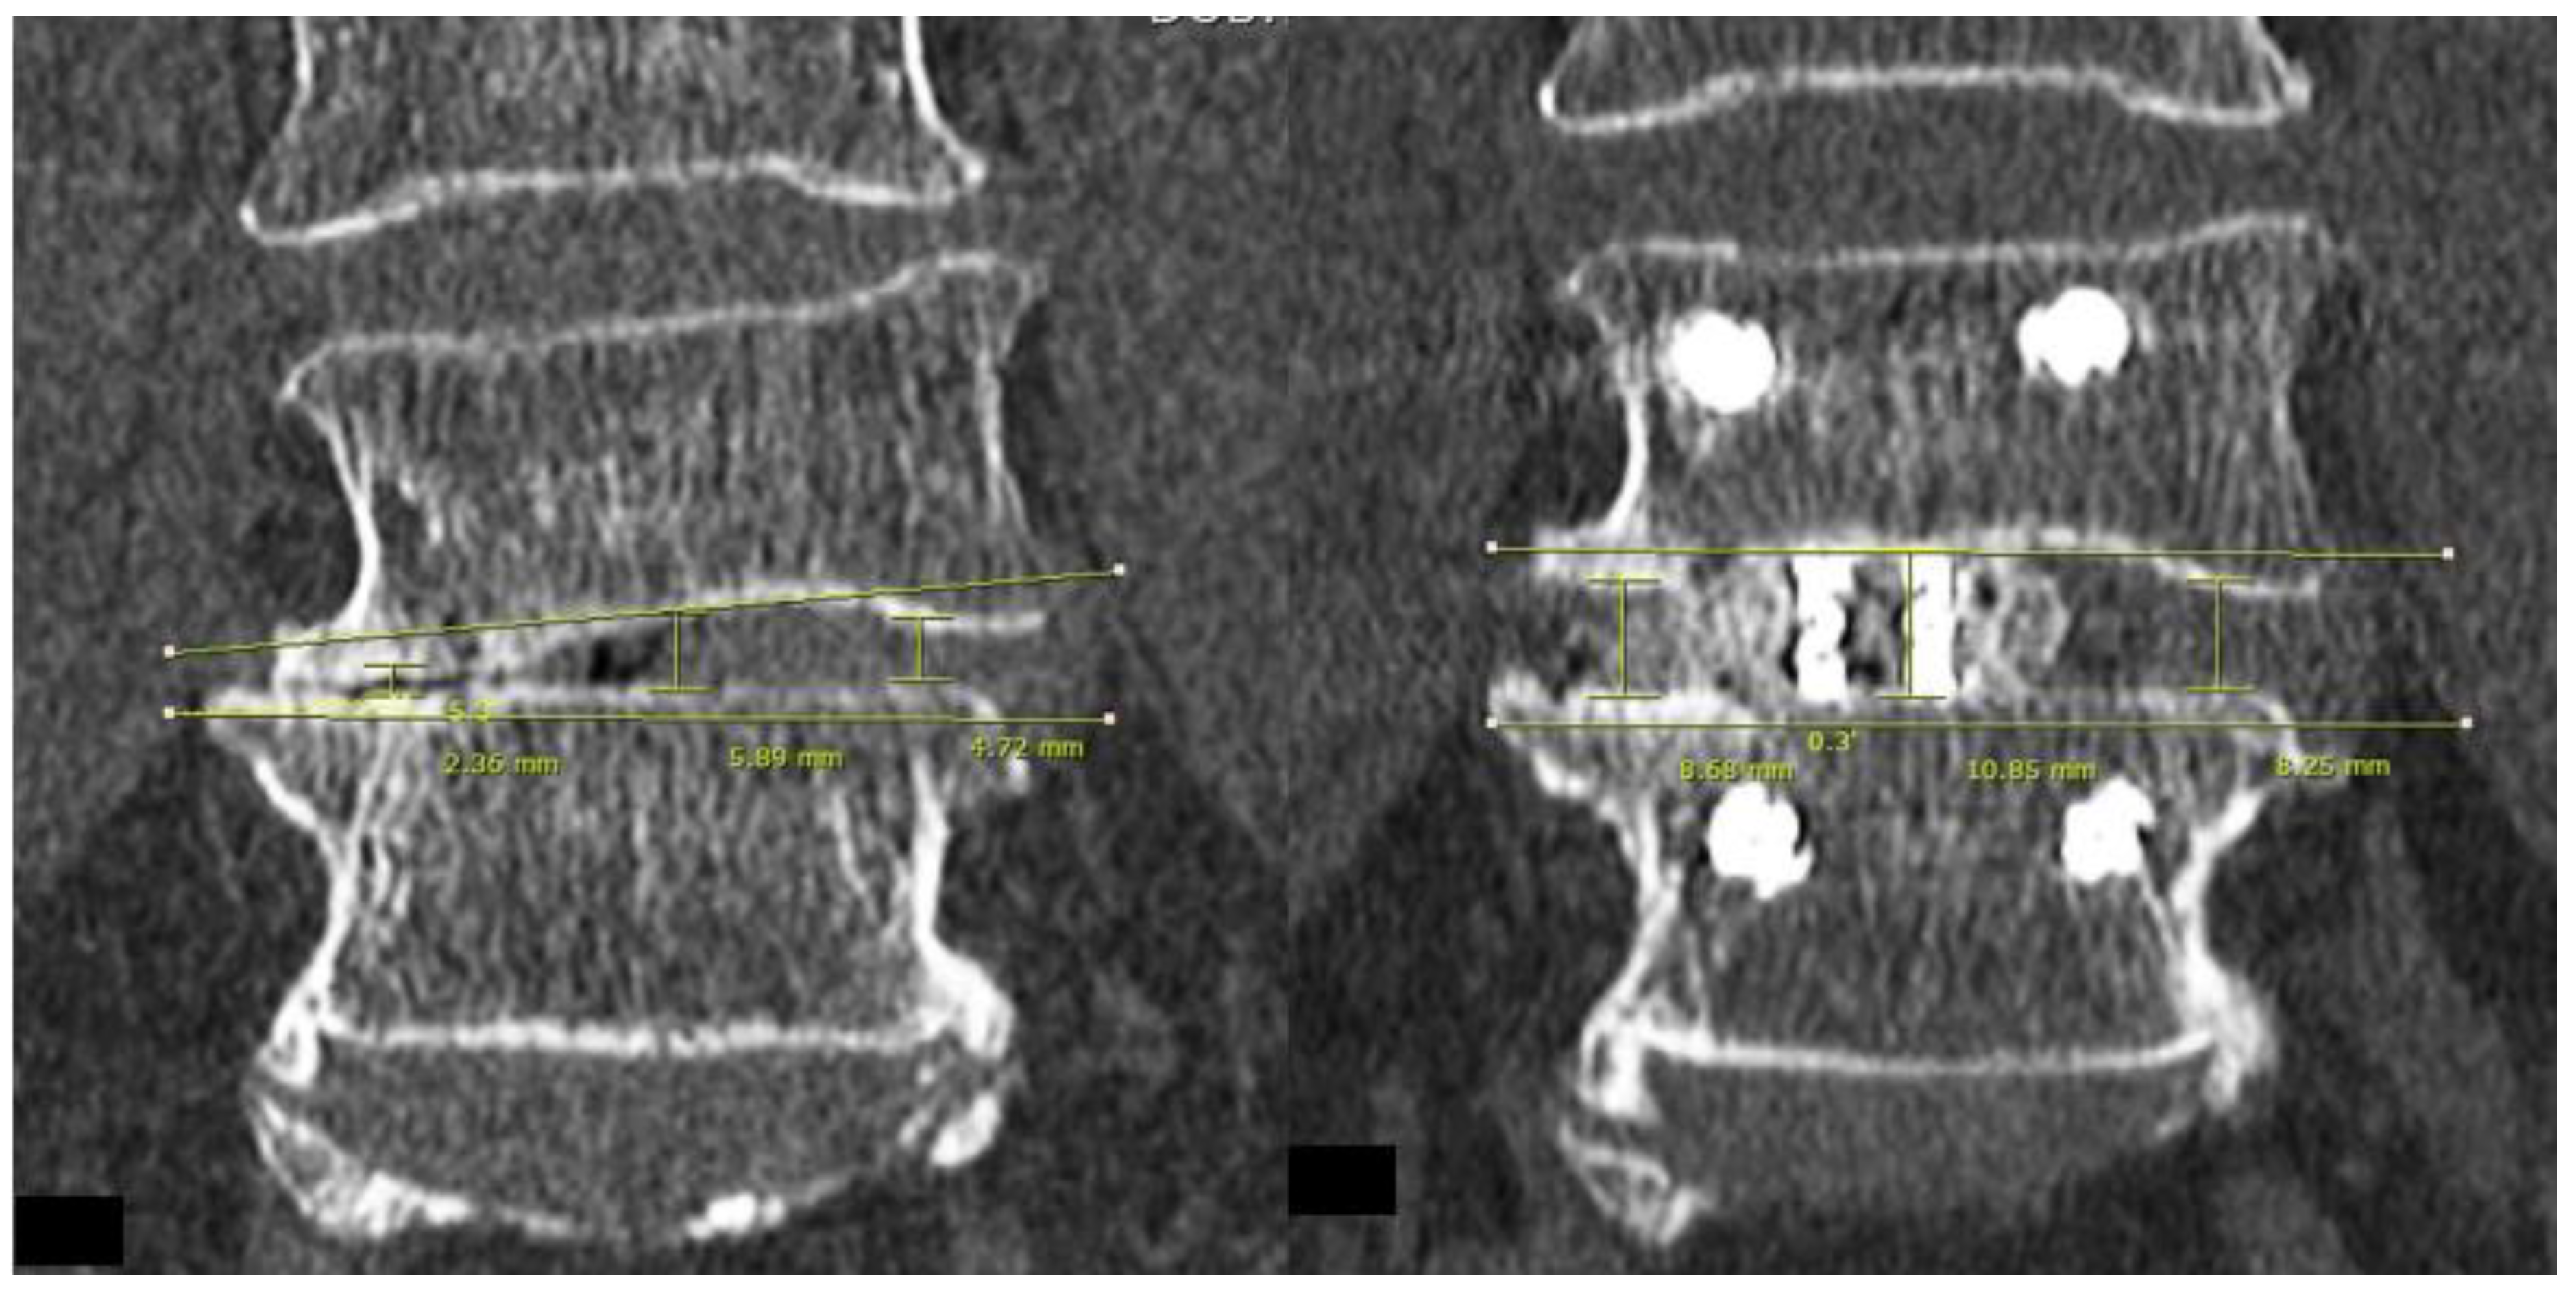

For post-operative evaluation in this cohort of patients, we evaluated clinical outcomes of Visual Analogue Scale at pre-operative, 1 week post-operative, 3 months post-operative and final follow up. Early and late perioperative complications were documented. For radiological evaluation, CT lumbar spine evaluation was done on pre-operative and post-operative day one. We evaluated mid sagittal CT lumbar spine to measure anterior, middle and posterior disc height and focal segmental angle (Figure 3). CT evaluation at mid coronal lumbar spine was done to measure mid coronal disc height and coronal wedge angle (Figure 4).

In terms of radiological results, the position of the implants was satisfactory in all cases. No subsidence of implants was found to have occurred in our cohort at final follow up XR. The means and ranges of pre-operative mid sagittal CT lumbar spine anterior, middle and posterior disc heights were 3.91 (1.71–6.99) mm, 3.8 (0.43–4.98) mm, and 3.84 (0.43–7.03) mm, respectively. The post-operative mid sagittal lumbar spine CT anterior, middle and posterior disc heights were 11.1 (8.18–15.6) mm, 10.2 (7.28–12.4) mm, and 9.12 (5.88–11.5) mm, respectively. The means and ranges of pre-operative and post-operative mid coronal lumbar CT disc height were 3.42 (0.43–4.98) mm, and 10.6 (6.59–14.5) mm, respectively. The pre-operative and post-operative mid coronal lumbar CT wedge angles were 8.02 (0.1°–19.3°) and 5.51 (0°–15.5°), respectively. The pre-operative and post-operative mid sagittal lumbar CT focal segmental angles were 10.9 (−3.4° to 27°) and 12.9 (−1.9° to 31°), respectively.

There was an increase in computer tomographic mid sagittal anterior, middle and posterior disc height of 6.99 (±2.30) mm, 6.28 (±1.43) mm, 5.12 (±1.79) mm, respectively, p < 0.05. Similar findings were shown in CT mid coronal disc height, with an increase of 7.13(±1.90) mm, p < 0.05. There was a significant improvement in CT coronal wedge angle in post-operative scan compared to the pre-operative scan of 2.35 (±4.73°), and in the mid sagittal CT focal segmental angle of 1.98 (±4.69°), p < 0.05.

Figure 3. Mid sagittal cut of CT lumbar spine for measurement of parameters with left picture showed pre-operative cut and right picture showed post-operative cut of mid sagittal CT lumbar spine. Anterior vertebral line was drawn for caudal vertebra (line A) and anterior disc height was measured from the line parallel to line A from the caudal end plate to the cephalad end plate. The posterior vertebra line was drawn for caudal vertebra (line B) and posterior disc height is measured from line parallel to line A from caudal end plate to cephalad end plate. Middle disc height is measured at the end plate in the midpoint of lines A and B (M point) to the corresponding cephalad vertebral body end plate.